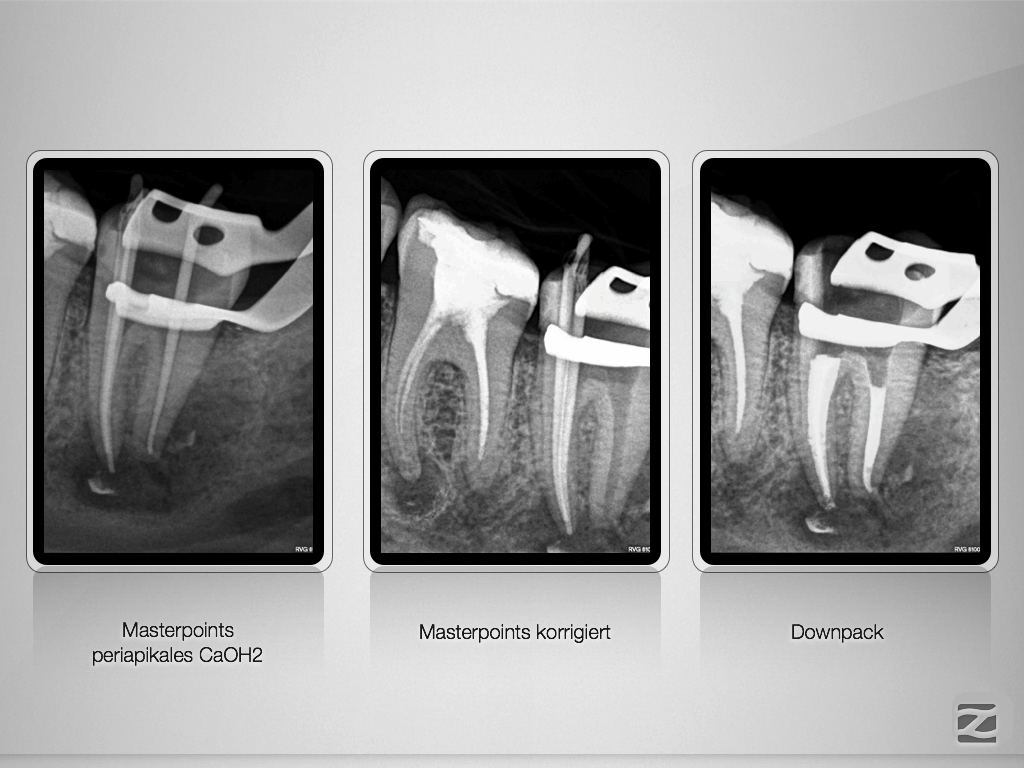

Ausgedehnte apikale Lyse